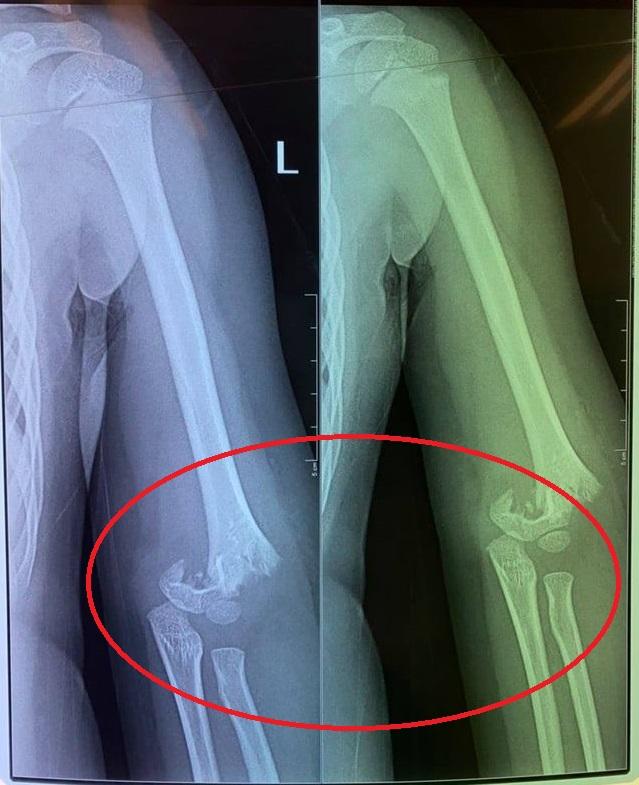

Con chị H. đã bị 1 bạn cùng lớp đẩy ngã từ cầu trượt văng ra ngoài làm gãy khuỷu tay. Tuy nhiên nhà trường lại không đưa bé T. đi bệnh viện luôn. "Tầm 12h trưa, tôi nhận được cuộc điện thoại của nhà trường báo: ''Con nhà chị sáng đi học bị ngã, tay sưng và đang cho lên bệnh viên Bạch Mai'. Sau đó tôi đi ra bệnh viện Bạch Mai thì cô hiệu trưởng báo bệnh viện Bạch Mai sẽ chuyển con lên bệnh viện Xanh Pôn. Tôi ngồi đợi con ở sảnh bệnh viện, đến khi cô hiệu trưởng đi ra thì thông báo: 'Mẹ làm hồ sơ nhập viện để mổ cho con'".

Con chị H. bị gãy phần khuỷu tay.

Chị H. cho biết, lúc nghe tin chị rụng rời tay chân, bàng hoàng không thốt nên lời. "Tôi đi vào phòng cấp cứu và được bác sĩ dặn phải thật bình tĩnh. Bác sĩ cho biết, may mà con tôi không bị liệt tay. Cháu bị gẫy tung khuỷu tay và phải được mổ ngay lập tức".